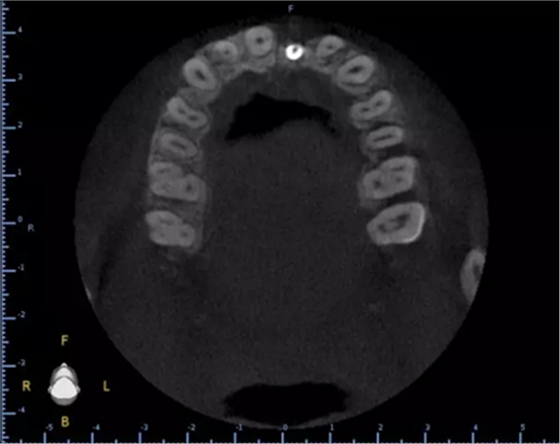

1.術(shù)前CT

2.術(shù)前植體設(shè)計(jì)

3.術(shù)前導(dǎo)板設(shè)計(jì)

術(shù)后CT